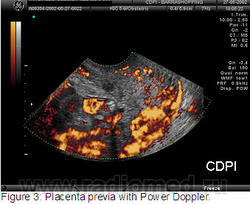

Клиника де Diagnóstico пор Imagem (CDPI), Институт Fernandes Figueira (IFF) - FIOCRUZ